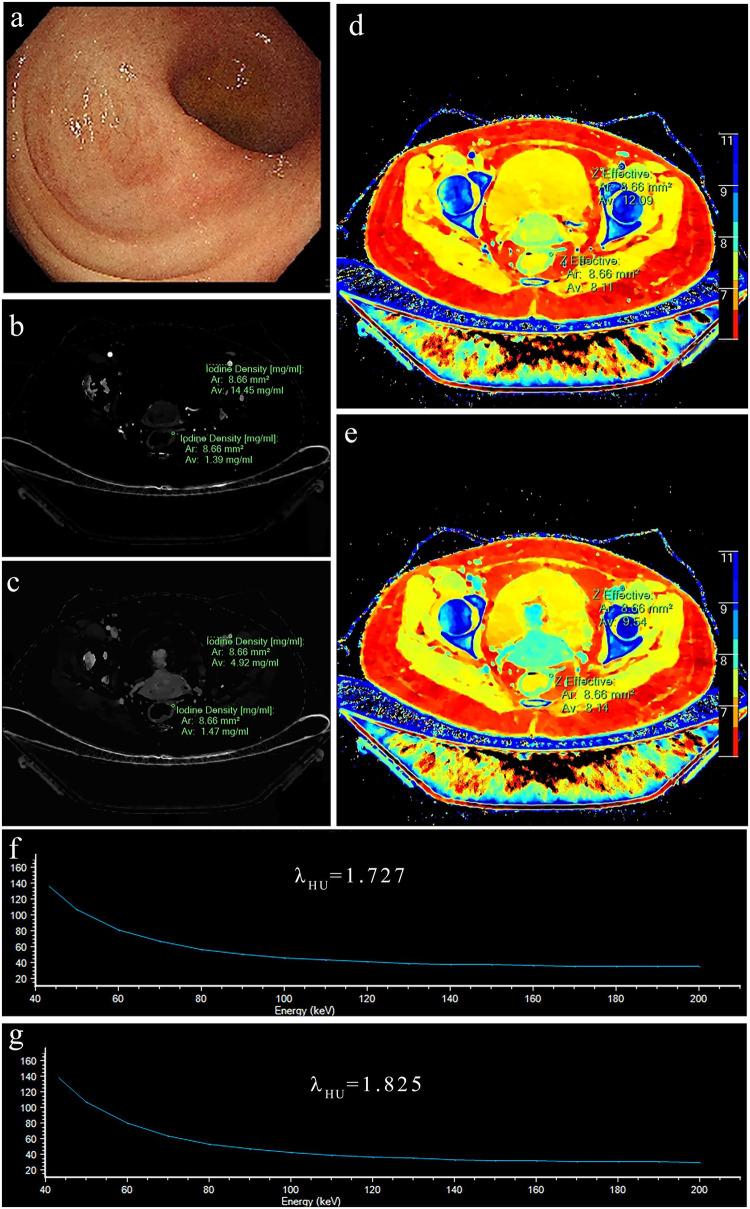

There were 110 active and 92 inactive bowel segments. In univariate analysis, the slope of spectral curve in the venous phases (λ-V) has the best diagnostic performance, with an area under the ROC curve (AUC) of 0.81 and an optimal threshold of 1.975. In the testing set, the AUC of the three models established by the 7 variables to differentiate CD activity was 0.81-0.87 (DeLong test p value was 0.071-0.766, p > 0.05), and the combined model had the highest AUC of 0.87 (95% confidence interval (CI): 0.779-0.959).

有110个活动肠段和92个非活动肠段。单因素分析中,静脉期光谱曲线斜率(λ-V)具有最佳诊断性能,ROC曲线下面积(AUC)为0.81,最佳阈值为1.975。在测试集中,由7个变量建立的用于区分CD活动度的3个模型的AUC为0.81-0.87(德龙检验p值为0.071-0.766,p>0.05),联合模型的AUC最高,为0.87(95%置信区间(CI):0.779-0.959)。